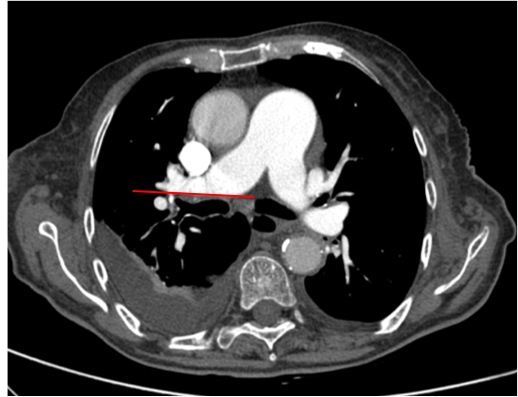

Defecto de repleción parcial periférico con rectificación de la pared de la arteria pulmonar derecha, sugestivo de estigmas de TEP crónico

Defecto de repleción parcial y periférico con ángulo obtuso en arteria lobar inferior derecha (amarillo), sugestivo de TEP crónico. Arteria lobar del LM con aumento de calibre y signo de angulo agudo, sugestivo de TEP agudo. Distal al trombro la arteria segmentaria ha disminuido el calibre por ausencia de flujo (rosa).